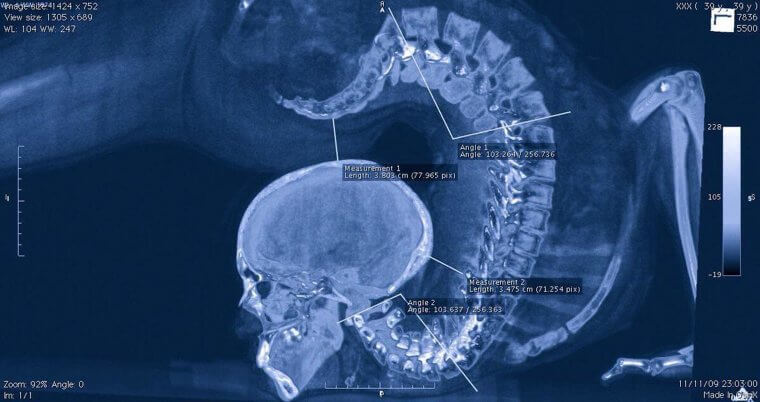

It's always fascinating to see athletes at the top of their game, whether in the Super Bowl, the World Cup, or in various events in the Olympics. People can do some incredible things with their bodies. What is really next level, though, is seeing how their bodies can accomplish these feats on the inside. This contortionist was x-rayed by scientists while performing a particular maneuver that should clearly only be attempted by well-trained professionals.

The trainer of this contortionist pointed out to the scientists how so much of her spine stays straight while doing this "head to butt" maneuver--he says that the secret of a successful backbend lies in a supple neck. We'll take his word for it.